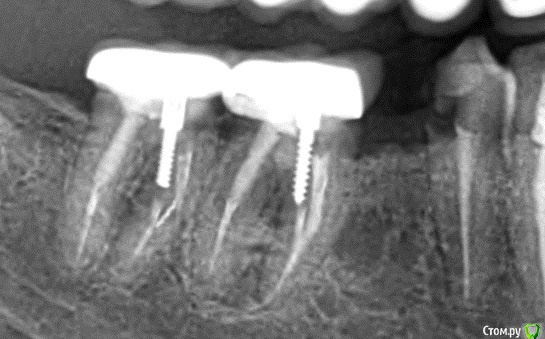

МартаМ Опубликовано 3 августа, 2017 Автор Поделиться Опубликовано 3 августа, 2017 Кт=компьютерная томография? Увы, я практически уверена, что у нас ее не делают((А на снимке никакого криминала не видно? Затемнение между корнями может свидетельствовать о чем-то нехорошем? Ссылка на комментарий

___49___ Опубликовано 3 августа, 2017 Поделиться Опубликовано 3 августа, 2017 (изменено) Кт=компьютерная томография? Увы, я практически уверена, что у нас ее не делают((А на снимке никакого криминала не видно? Затемнение между корнями может свидетельствовать о чем-то нехорошем?Кт - Комп.томография. Затемнение не четко выражено - требует комплексного подхода из осмотра, сбора анамнеза, Rснимка для решения задачи . у вас был или есть свищ(прыщ) на десне около 6 ки ? Изменено 3 августа, 2017 пользователем ___49___ Ссылка на комментарий

Doc Опубликовано 5 августа, 2017 Поделиться Опубликовано 5 августа, 2017 В межкорневой зоне явное разрежение. Либо бифуркация, либо перфорация. И то и другое - повод для удаления. Но по одному снимку диагноз нельзя ставить и тем более удалять зуб. 1 Ссылка на комментарий

МартаМ Опубликовано 10 августа, 2017 Автор Поделиться Опубликовано 10 августа, 2017 В межкорневой зоне явное разрежение. Либо бифуркация, либо перфорация. И то и другое - повод для удаления. Но по одному снимку диагноз нельзя ставить и тем более удалять зуб.Врач уверяет, что затемнение вызвано тем, что зуб разрушен глубоко под десну, а боль - невралгия. У невролога была, проблем не обнаружили. Ссылка на комментарий

Doc Опубликовано 10 августа, 2017 Поделиться Опубликовано 10 августа, 2017 Врач уверяет, что затемнение вызвано тем, что зуб разрушен глубоко под десну, а боль - невралгия. У невролога была, проблем не обнаружили.Собственно, если зуб разрушен глубоко под десну, то именно это и есть показание к удалению, а невралгия тут не причем. 1 Ссылка на комментарий